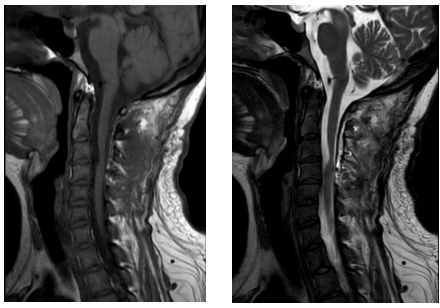

术后复查颈椎核磁显示病变全切除,受压的脊髓部分复原

经神经外科团队研判,杭女士病情指征符合手术条件。在与患者及家属沟通后,神经外科团队为患者量身定制了手术方案。9月11日手术当天,患者采取俯卧位,头架固定头部,颈部后正中入路。显微镜下见病变呈囊性,位于颈3-4水平硬脊膜下脊髓腹侧面,抽吸囊液为灰白色,张力下降后将囊壁完整切除。囊壁为灰黄色,与脊髓腹侧面黏连紧密,血供不丰富,可见白色钙化颗粒。术毕将椎板复位,患者清醒后无新发神经功能缺损。术后两周时出院,患者颈肩痛明显缓解,四肢活动自如。术后复查颈椎核磁显示病变全切除。病理结果为肠源性囊肿。